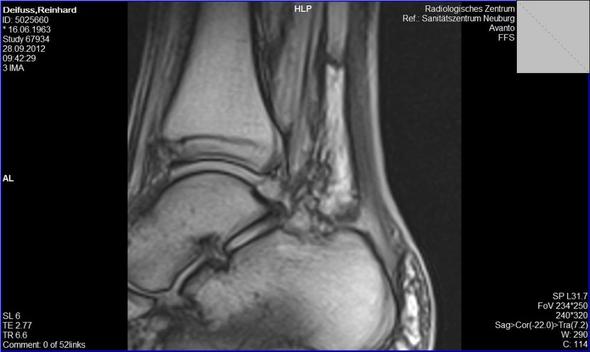

Chronik Einer Sprunggelenkfraktur Sky Junkies